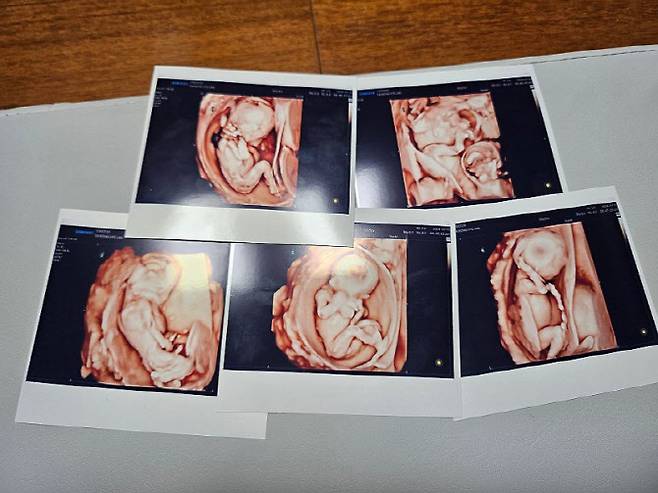

임신을 확인한 것은 뱃속 아기들이 5∼6주 차쯤 됐을 무렵인 4월께였다. 김씨는 아기집 5개를 확인했을 당시 심정을 묻는 말에 “교직에 있으니 아이들을 좋아하고, 자녀 계획을 세우는 데 영향이 있긴 했다”면서도 “자녀 한두명을 생각했었는데 다섯을 가질 줄은 몰랐다”고 털어놨다.

그러면서 “(아기집을 보고) 첫 2주간 둘이서 맨날 울었다”며 “다섯쌍둥이가 생겼다는 사실을 받아들이기 힘들었다”고 말했다.